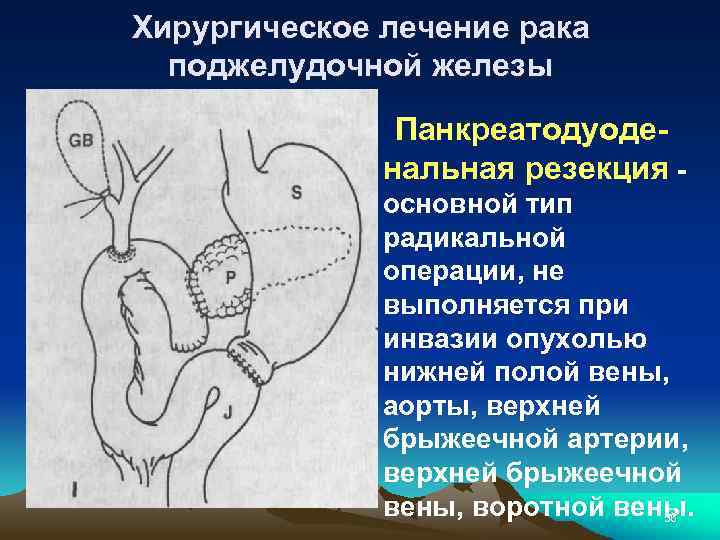

Хирургическое лечение рака поджелудочной железы Панкреатодуоде- нальная резекция - основной тип радикальной операции, не выполняется при инвазии опухолью нижней полой вены, аорты, верхней брыжеечной артерии, верхней брыжеечной вены, воротной вены. 56